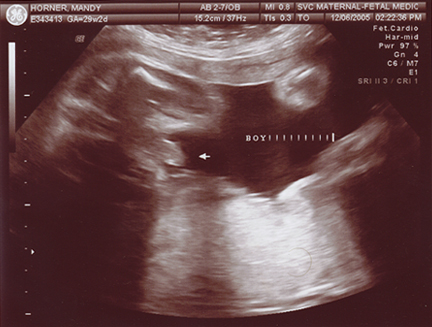

December 10, 2005 - Mandy has gone in for her doctor's appointments, and Evan is doing very well! He is a little over 2 pounds, and he is at 29 to 30 weeks! He is a very active little fellow, Manders can definately tell you that! We plan to go to Sioux Falls at least twice a week when Mandy is at 32 wks. She will undergo NoStress tests. Mandy has a lot better details for you than I would! She always keeps up with Evan on her LiveJournal site!